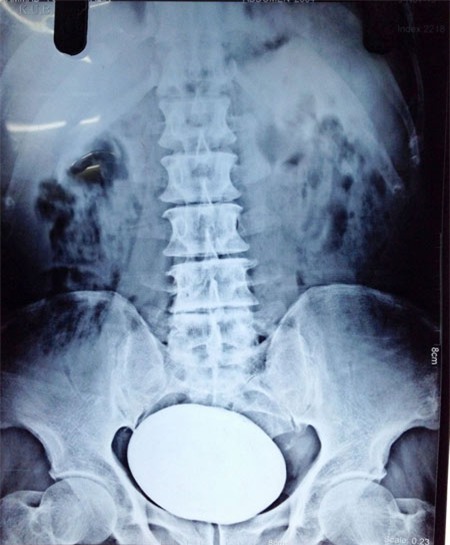

Ảnh chụp hòn đá nằm trong bàng quang bệnh nhân trước khi phẫu thuật.

Người đàn ông 65 tuổi Mohammad Yousuf Khan ở Kashmir, Ấn Độ vừa được phẫu thuật lấy ra một hòn đá nặng gần 1 kg từ bàng quang.

Bác sĩ xác nhận, hòn đá nặng 834g, lớn nhất từng được lấy ra từ bàng quang của bệnh nhân.